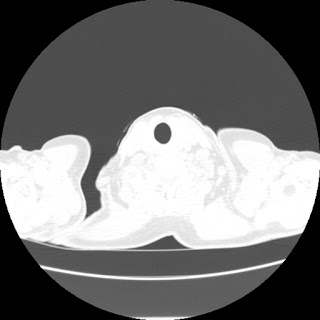

A 62 years old man with enlarged mole on chest since 2 months.

CT chest :-